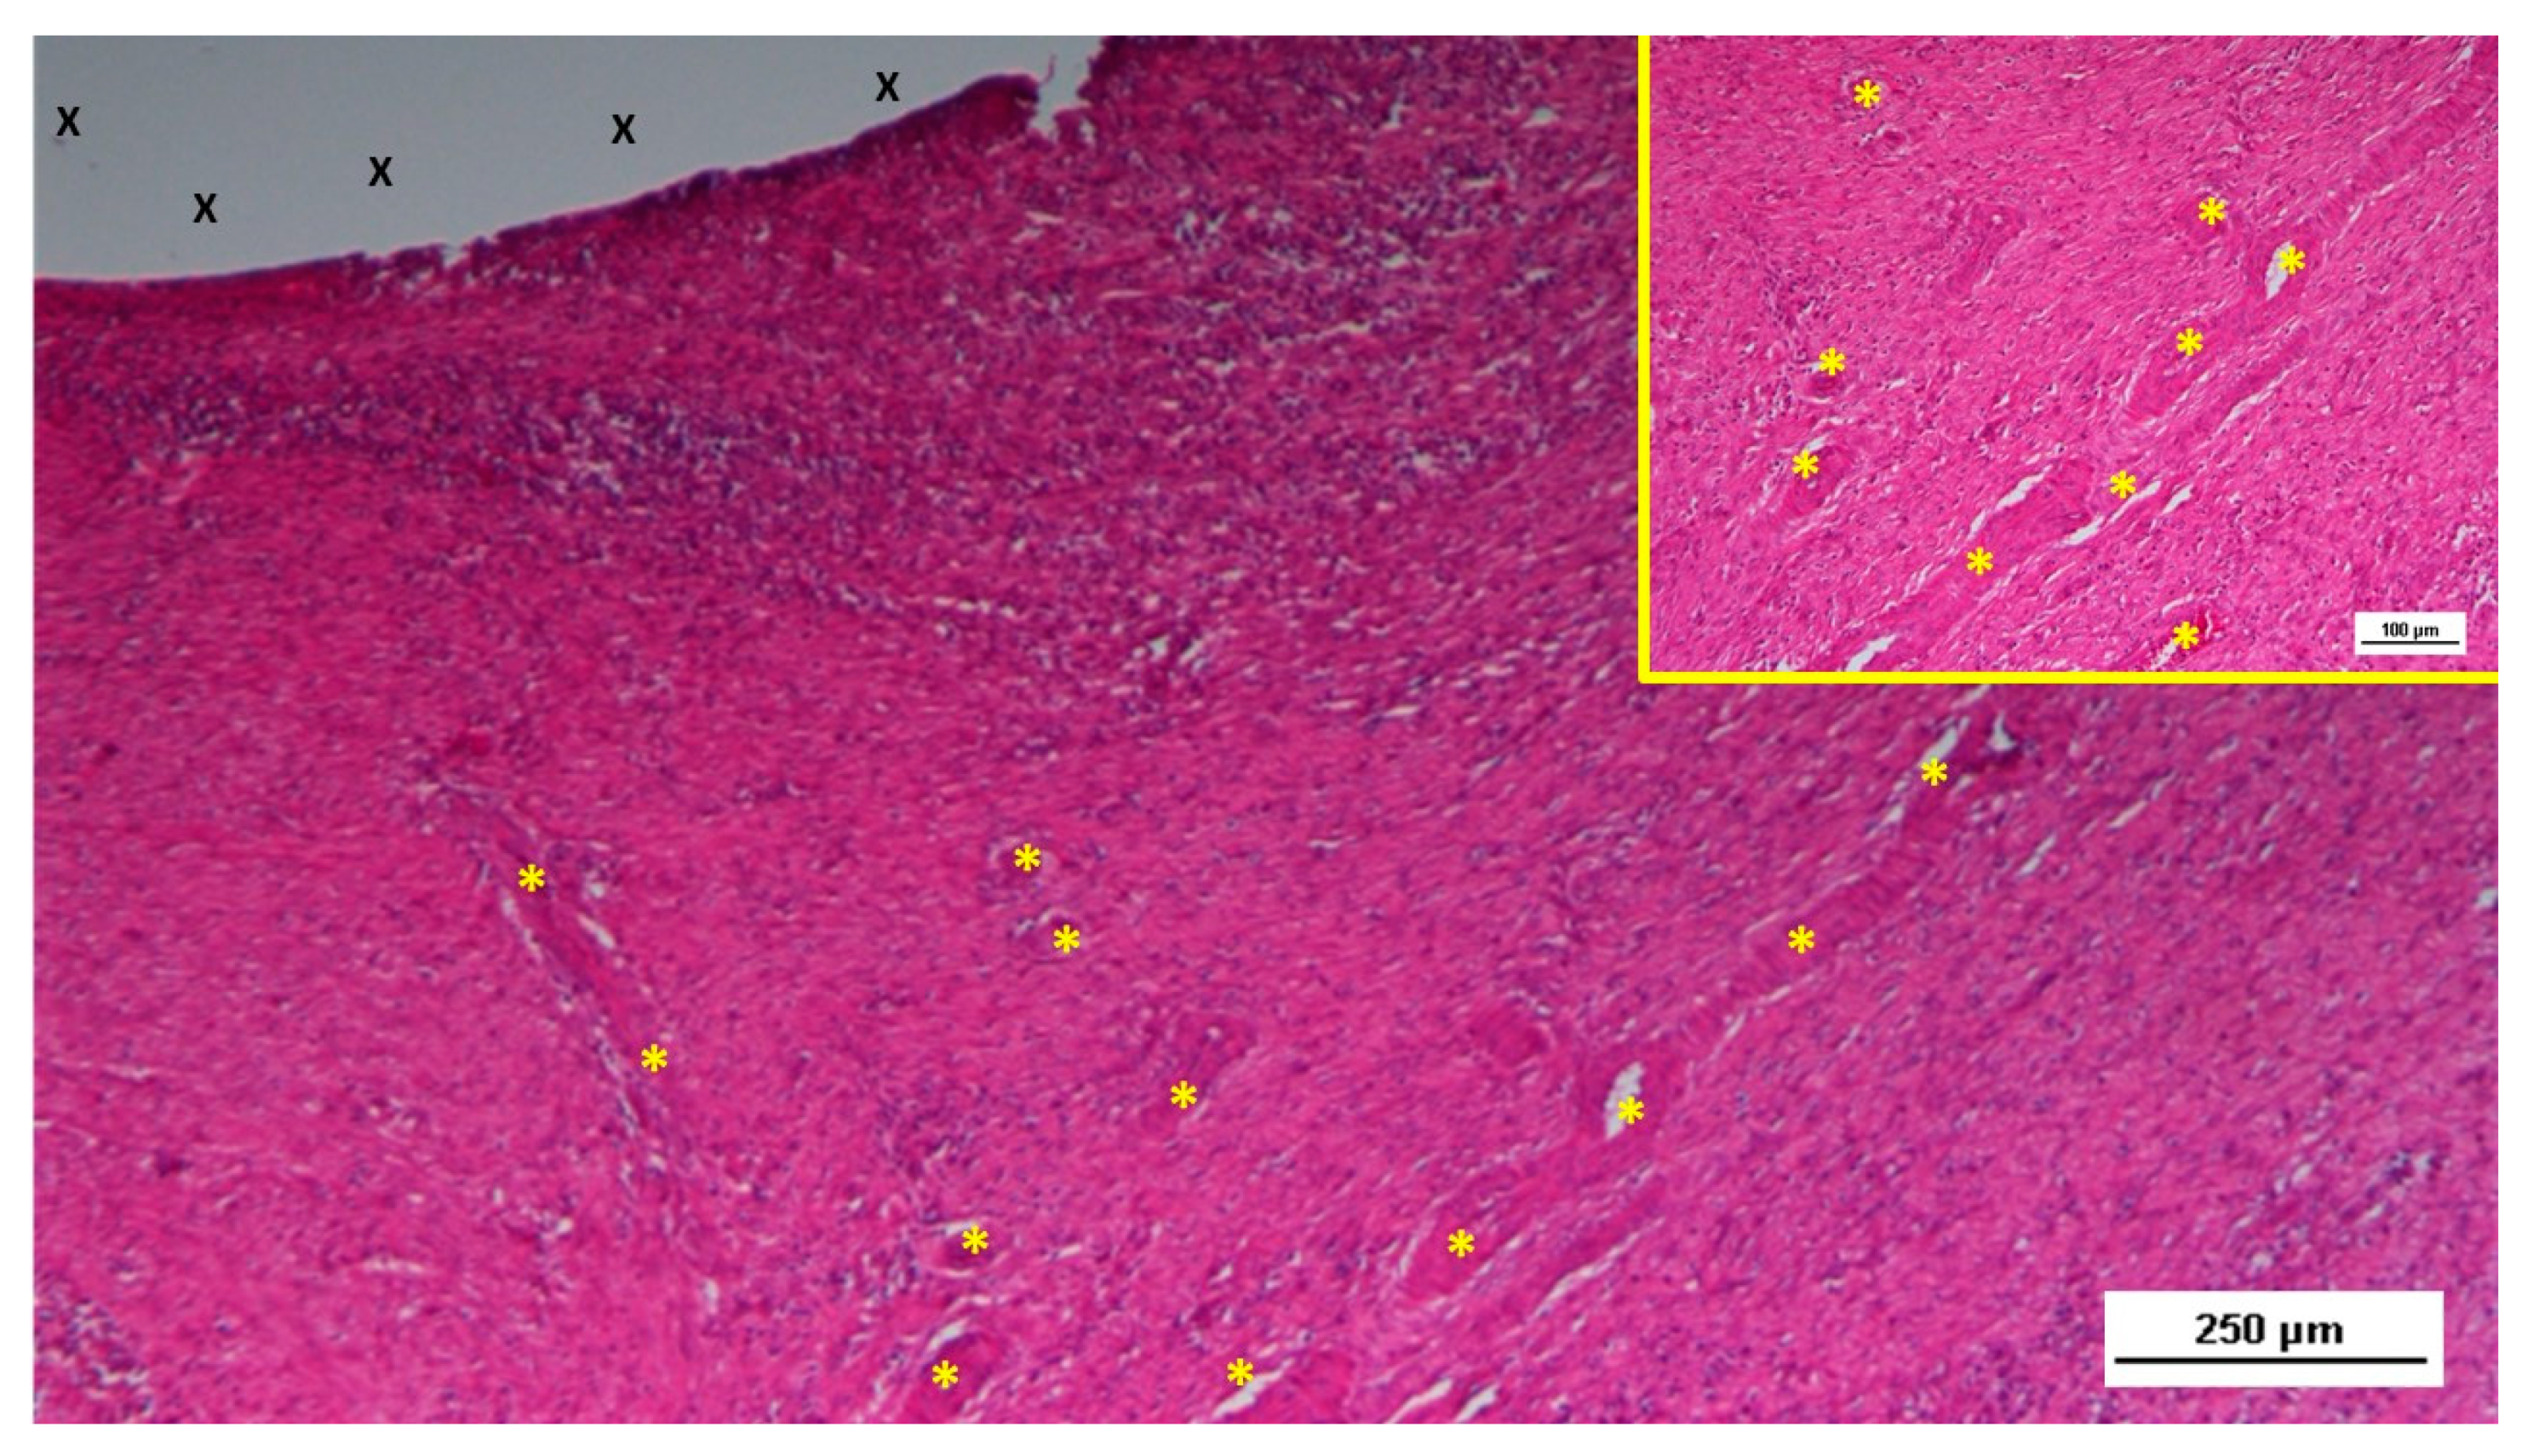

6-8 months post-implantation (long-term stage), there was a complete absence of inflammation, and the newly formed arteries and veins demonstrated full structural maturation across all components (Figure 11, Figure 12, Figure 13, Figure 14 & Figure 15).

In the short term, the histological analysis revealed the presence of immature vascular structures, indicative of early-stage angiogenesis. By the mid-term, a more extensive and organized vascular network had formed, with ongoing vascular development occurring inside the structure of the S&S device. In the long-term phase, the study observed the continued maturation of these vascular elements, which paralleled the development of other tissue components, particularly muscle fibers and nerves. By this stage, the muscular layer of the arterial and venous walls had fully matured, demonstrating the establishment of a competent vascular network capable of sustaining the newly formed, sophisticated tissues within the scaffold. In this final phase of vascular development, all vessel elements—arteries, veins, and capillaries—exhibited the structural characteristics of fully matured vessels. This well-established vascular network ensures adequate blood supply to the newly formed tissues, particularly muscle and nerve tissues, within the S&S device. All these evidences have been confirmed in detail by the statistical assessment.

Figure 12. Biopsy specimen from the 3D scaffold of the S&S device, six months post-surgery. In a matrix of slack, well-perfused connective tissue, several fully developed arterial structures (*) with thickened media are visible. A mature vein (Y) is located near the 3D scaffold fabric (X), which is free from inflammatory infiltration. HE 100X.